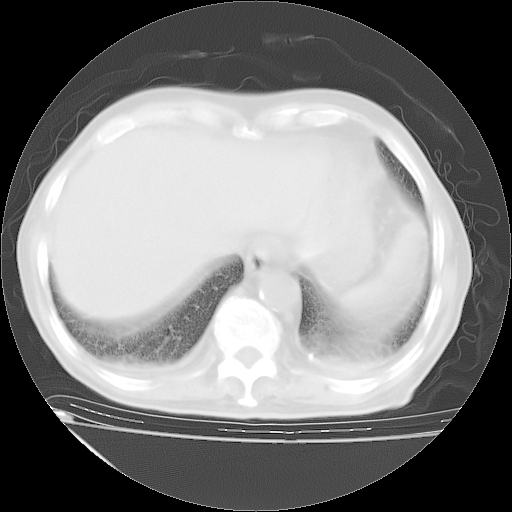

经过24天治疗,岳父的病情基本稳定。生活基本可以自理,可以下床活动。呼吸困难早已消失。体温基本正常。

主要治疗甲强龙80mg×14天,60mg×10天;同时抗结核(异烟肼+利福平+乙胺丁醇)。环磷酰胺0.1 tid 10天。

特别感谢胡教授、高管、桃子版主给出关键的治疗建议。桃版把所有肺部影像和全部临床资料请所在医院呼吸科、感染病科、结核科、临床免疫科专家会诊。临床免疫科专家制定了完整的治疗方案。